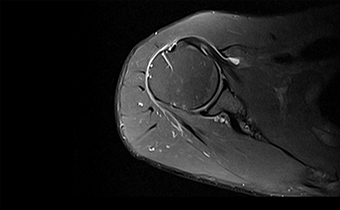

能在1秒内完成对任意部位,任意区域的快速精准匀场。磁场均匀度可达0.002ppm。在极速匀场过程中,几乎不受运动伪影的影响。

呈现大FOV、偏中心优质图像;实现大范围压脂成像,缩短压脂序列时间

改善脂肪抑制效果,减小DWI图像伪影。改善SWI等对B0涡流敏感序列的图像质量